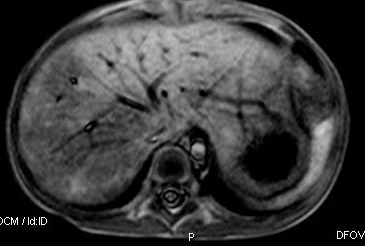

标题: V0176(MRI):小儿发热,肝脾大,肝内病变 [打印本页]

标题: V0176(MRI):小儿发热,肝脾大,肝内病变

5岁,2006年8月曾行阑尾炎手术,现发热半年